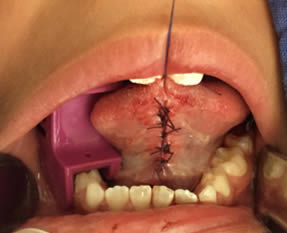

• Se irrigó bien la zona operatoria con solución fisiológica, se secó con gasa estéril, se revisó la hemostasia encontrándose en condiciones normales y se realizaron puntos simples de sutura utilizando Vicryl 3-0. Se terminó el acto quirúrgico sin accidentes ni incidentes. Figuras 11 y 12.

Figuras 11 y 12. Sutura y terminado del acto quirúrgico.

• Se entregaron indicaciones postoperatorias de manera verbal y escrita a los padres del paciente. La farmacoterapia utilizada fue Amoxil (Amoxicilina) en suspensión de 250mg en 5ml (8 ml cada 8 horas por 08 días) y  Motrin (Ibuprofeno) en suspensión de 100mg en 5ml, (12 ml cada 8 horas por 3 días).Se citó en 8 días para retiro de sutura, revisión y evaluar alta.